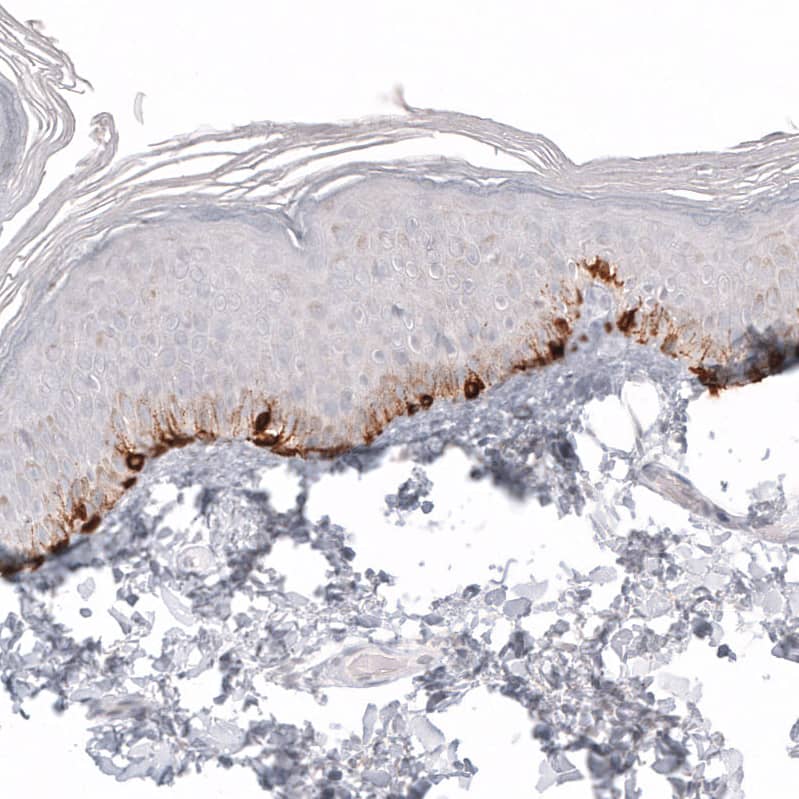

Staining of human skin shows strong cytoplasmic positivity in melanocytes.